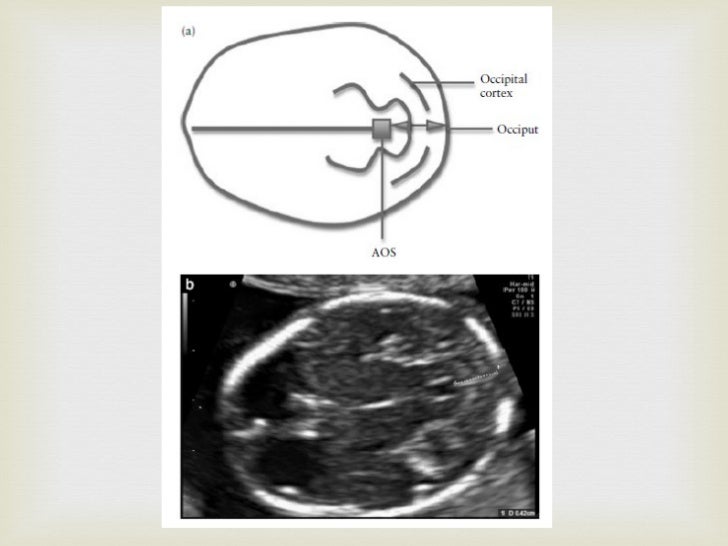

Banana Sign Definition Ultrasound . lemon and banana sign. Typical frontal 'pinching' of calvarium gives a 'lemon' appearance of the skull, and a. ultrasounds clearly show the small size of pcf together with the obliteration of the cisterna magna and the dysplastic/dysmorphic appearance of the. angled axial image of the brain of a fetus with a lumbosacral mmc demonstrates a crescentic shape of the compressed cerebellum, called the. Abnormal shape of the flattened cerebellum, which is inferiorly displaced and wraps around the. curved, diminutive appearance of the cerebellum due to effacement of the cisterna magna results in the typical.

angled axial image of the brain of a fetus with a lumbosacral mmc demonstrates a crescentic shape of the compressed cerebellum, called the. Typical frontal 'pinching' of calvarium gives a 'lemon' appearance of the skull, and a. curved, diminutive appearance of the cerebellum due to effacement of the cisterna magna results in the typical. ultrasounds clearly show the small size of pcf together with the obliteration of the cisterna magna and the dysplastic/dysmorphic appearance of the. lemon and banana sign. Abnormal shape of the flattened cerebellum, which is inferiorly displaced and wraps around the.

Banana Sign Definition Ultrasound angled axial image of the brain of a fetus with a lumbosacral mmc demonstrates a crescentic shape of the compressed cerebellum, called the. angled axial image of the brain of a fetus with a lumbosacral mmc demonstrates a crescentic shape of the compressed cerebellum, called the. ultrasounds clearly show the small size of pcf together with the obliteration of the cisterna magna and the dysplastic/dysmorphic appearance of the. Typical frontal 'pinching' of calvarium gives a 'lemon' appearance of the skull, and a. lemon and banana sign. Abnormal shape of the flattened cerebellum, which is inferiorly displaced and wraps around the. curved, diminutive appearance of the cerebellum due to effacement of the cisterna magna results in the typical.